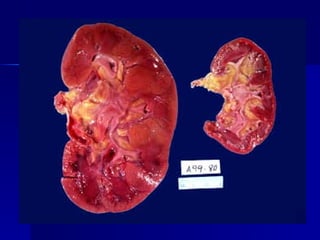

HIPERTROFIA - Aumento deltamaño de un órgano o tejido por aumento del tamaño celular y aumento de su función. - Aumento de componentes celulares y estructurales. - El Útero es receptor estrogénico en el músculo liso: proteína y ADN: hipertrofia fisiológica. - Músculo estriado y cardiaco: mayor capacidad de hipertrofia. - Aumento de síntesis de proteínas y miofilamentos.

- Demanda funcionalaumentada. Músculos, hipertrofía cardiaca por hipertensión, hepatocitos (aumento de REL por estímulo de fenobarbital y drogas hipolipemiantes)- hepatomegalia fisiológica - Hipertrofia del riñón contralateral. - Más frecuentes en tejidos pemanentes y estables.

Cell Injury Cell Injury Hypertrophy- gross Hypertrophy - gross